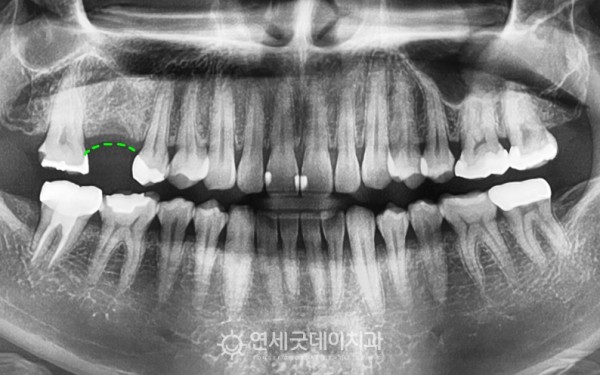

치아가 빠진지 약 1년 정도 지나서

어금니 임플란트를 주소로 내원해주신 환자분입니다.

치아가 빠진채로 약 1년 가량 방치되면서

어금니 부위의 잇몸뼈 수축이 관찰되는 모습입니다.

치아를 발치한 채로 두게되면,

보통 6개월 이내에 수평적으로 4mm

수직적으로 1.5mm 정도가 감소되며

임플란트를 심기에는

잇몸뼈의 두께가 다소 얇을 수 있습니다.

환자분은 다행히 잇몸뼈 소실이

아주 심한 편은 아니셨기에

상악동수술이 아닌 잇몸뼈이식을 동반하여

어금니 임플란트 치료계획을 세웠습니다.